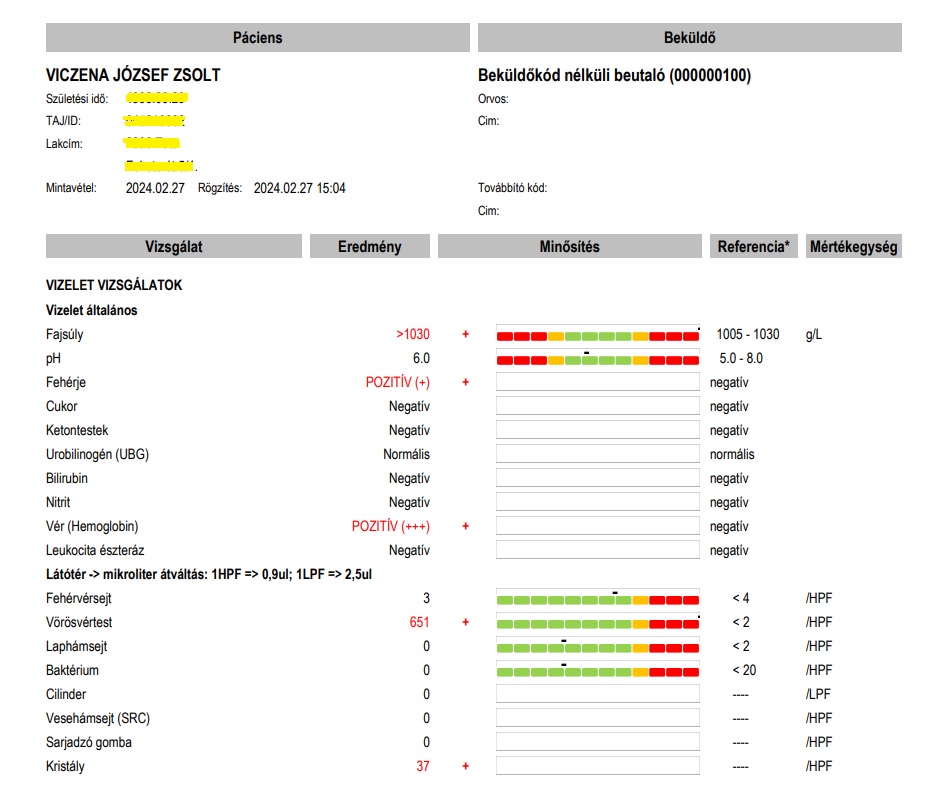

Február 26 után (fentebb), Február 27-én, Dr Barna István rendelése után csupán 5 nappal, ismét kibuggyant a vérvizelés, az alábbi súlyos eredménnyel:

Több százszoros vérvizelési érték (651 VVT/látótér), 3 keresztes vérzés. A fiam úgy döntött, mivel szinte most volt Dr Barna Istvánnál, megkérdezi emailben, hogy „most akkor hogyan tovább? Mi a következő lépés?” Azt remélte, hogy azonnal behívja a klinikára, és most már épp elég objektív bizonyíték után, azonnal fel is veszi. Válasz sem akkor, sem az azóta eltelt 2 év alatt nem érkezett! Egy 30 éves ember, aki nincs egy hete, hogy kifizetett 40 ezer forintból már nem érdemelt meg egy választ az akut állapotú fiam. Hol az orvosi felelősség és eskü?